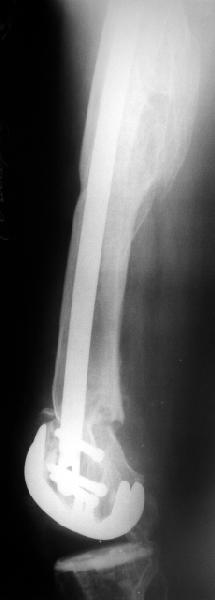

В итоге сделали антеградный остеосинтез. В дистракторе свежий перелом вправился сразу, а вот старый - оставил проблему, дистальный отлмомк остался все равно кзади. И гвоздь бы прошел кпереди от него, а ретроградный - перфорировал бы передний кортекс. Так что пришлось еще сделать чрескожную остеотомию через перелом, чтобы малость мобилизовать дистальный отломок. Снимки в прилжении.